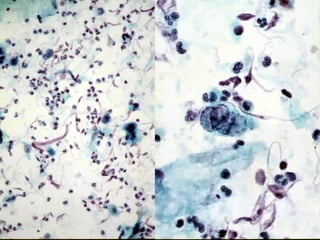

Pulmonary InfectionPulmonary Infection

• Viral infection

– BAL diagnosis

– Cilicytophthoria: detachment of cilia

• Adenovirus infection

– Reactive epithelial atypia

– Specific viral inclusions

Pulmonary InfectionPulmonary Infection •Viral infection – BAL diagnosis – Cilicytophthoria: detachment of cilia • Adenovirus infection – Reactive epithelial atypia – Specific viral inclusions